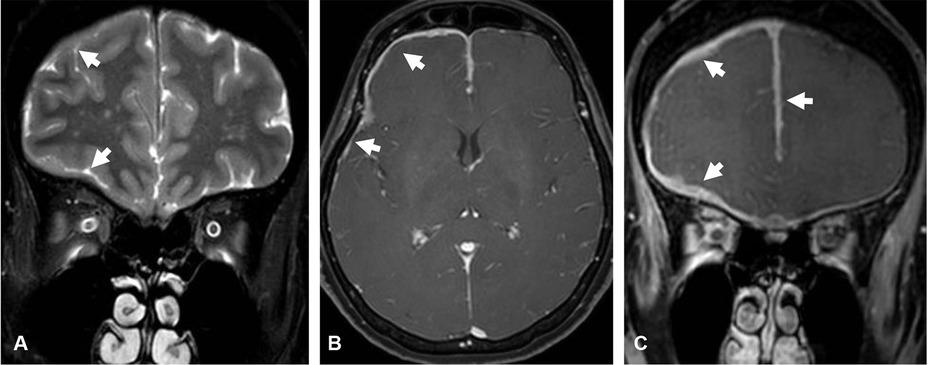

Figure 4